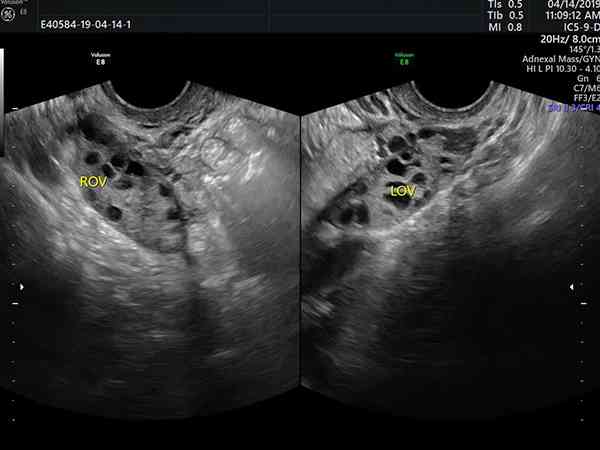

看优势卵泡有没有排出有很多种方法,最常用的方法还是做B超监测。每一个周期卵巢都会产生很多卵泡,有的卵泡发育过程中就开始萎缩,有的卵泡发育成熟后自然排出,但是往往只有一个卵泡会发育成熟形成直径为18mm-22mm足有的优势卵泡。通常做卵泡监测的时间会长达三个月的时间,没有优势卵泡就无法正常受孕也没有办法优生优育,所以要定期监测卵泡的情况,在备孕的期间一定要养成一个良好的作息习惯,避免熬夜;同时要保持...

两天后发现优势卵泡消失,一般是排卵了,因为卵泡在排出后会直接消失,而萎缩可以明显观察到卵泡变小。女性每个月有3-20枚的卵泡发育,但其中只有1枚卵子能够发育成熟并跟精子结合形成受精卵,剩下的卵泡会逐渐萎缩直至消失,而这个时间段通常被人们成为排卵期,也是女性每个月怀孕黄金期,所以在这个期间同房,能增加怀孕几率。B超监测排卵一般是在月经周期第10天开始进行,观察卵泡直径的变化,在排卵前4天的卵泡直径平...